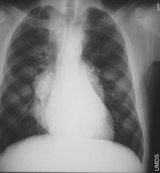

Dünya genelinde ölümlerin yaklaşık % 20’si akciğer hastalıklarına bağlı nedenlerden meydana geliyor. Yılda yaklaşık 4 milyon kişi KOAH nedeniyle yaşamını kaybediyor. Her yıl 3 milyon kişi pnömoni, 2 milyon kişi ise akciğer kanseri gibi akciğer sorunları nedeniyle ölüyor. Türkiye’de akciğer kanseri vakası yılda 15 bini geçiyor.

Dünyada her yıl yüz milyonlarca insanın tüberküloz, astım, pnömoni, influenza, akciğer kanseri ve KOAH gibi solunum hastalıklarından muzdarip olduğunu belirten SOLUNUM 2010 Kongre Başkanı Doç. Dr. Filiz Koşar, “Her yıl dünya genelinde 10 milyondan fazla kişi bu nedenlerle hayatını kaybediyor. Kronik solunum hastalıkları dünyadaki bütün ölümlerin % 7’sini ve toplam hastalık yükünün % 4’ünü oluşturuyor. Dünya genelinde ölümlerin yaklaşık % 20’si akciğer hastalıklarından kaynaklanıyor. Bu hastalıklar, mortalite açısından üçüncü sıradadır” dedi.

Solunum hastalıklarının dünyada ve Türkiye’de önemli bir mortalite nedeni olmaya devam ittiğini söyleyen Prof. Dr. Can Öztürk, “Yılda yaklaşık 4 milyon kişi KOAH nedeniyle yaşamını kaybediyor. Her yıl 3 milyon kişi pnömoni, 2 milyon kişi ise akciğer kanseri gibi sorunlar nedeniyle ölüyor. KOAH’lı hastalar yetişkin nüfusun %10’unu oluşturuyor ve sadece Avrupa ülkelerinde yılda 30 milyar Euro’luk ekonomik kayba neden oluyor. Buna, Astım, Akciğer Kanseri, Pnomoni, Tüberküloz gibi hastalıkları da eklersek, sadece AB ülkelerinin bu sorun için her yıl 100 milyar Euro’nun üzerinde harcama yaptığını görürüz” diye konuştu.